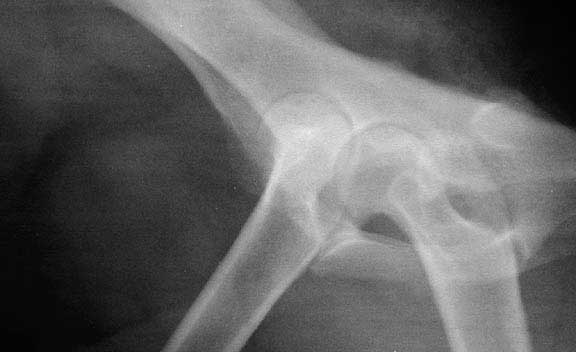

This is the lateral view where the dog is laying on its side

This x-ray is of a dog with a dislocated hip. The ball of the left femur is completely out of the socket. Ligaments and the joint capsule have been torn for this to occur.